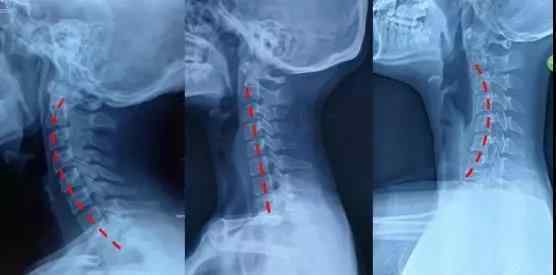

正常人去看电影,81%有问题

从1993年开始,日本学者对497名平均年龄35岁的正常人进行了20多年的研究。结果表明,81%的患者在磁共振成像上有颈椎间盘退变或突出。颈椎的曲线与是否会发展成颈椎病没有明显的相关性。

很多正常人去拍片,颈椎也不完全正常。颈椎疼痛和异常在片子上没有完全的因果关系。

X线片、CT、MRI如何选择?

x光片:原理是用x光穿透身体,形成图像,就像拍照一样。对了解颈椎的整体情况很有帮助,是很多医生的首选。